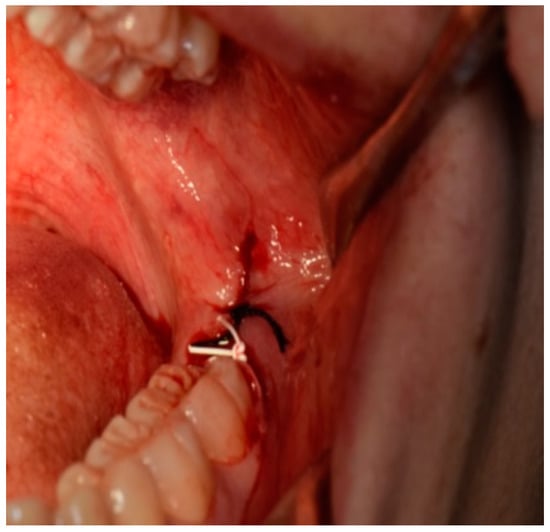

All patients received oral hygiene performed by a professional oral hygienist 10 days before surgery and were educated on the correct home oral hygiene. All interventions and suture placements were performed by the same surgeon with more than 20 years of experience in oral surgery (S.P.): after local anesthesia with articaine 1:100.000, an incision was performed distally to the second mandibular molar with vestibular release incision. Further, a full-thickness mucoperiosteal flap was elevated; osteotomy around the mandibular third molar crown was then performed with bur, the tooth was dislocated with a straight lever and it was then completely removed with pliers. Accurate alveolar revision was then performed, and a saline lavage was performed inside the alveolus. After the tooth removal, two sutures with different materials were applied on the surgical site in order to obtain a first intention closure: one single stitch with 3/0 silk; one single stitch with 3/0 PTFE (Figure 1). Three knots per single stitch were used for both sutures: the order of the sutures was the same for all the patients involved in the study, with the PTFE placed distal to mandibular second molar and silk suture placed distal to PTFE suture.

Figure 1. Image of PTFE and silk suture after M3M surgery placed distally to the second molar with a first intention closure technique.